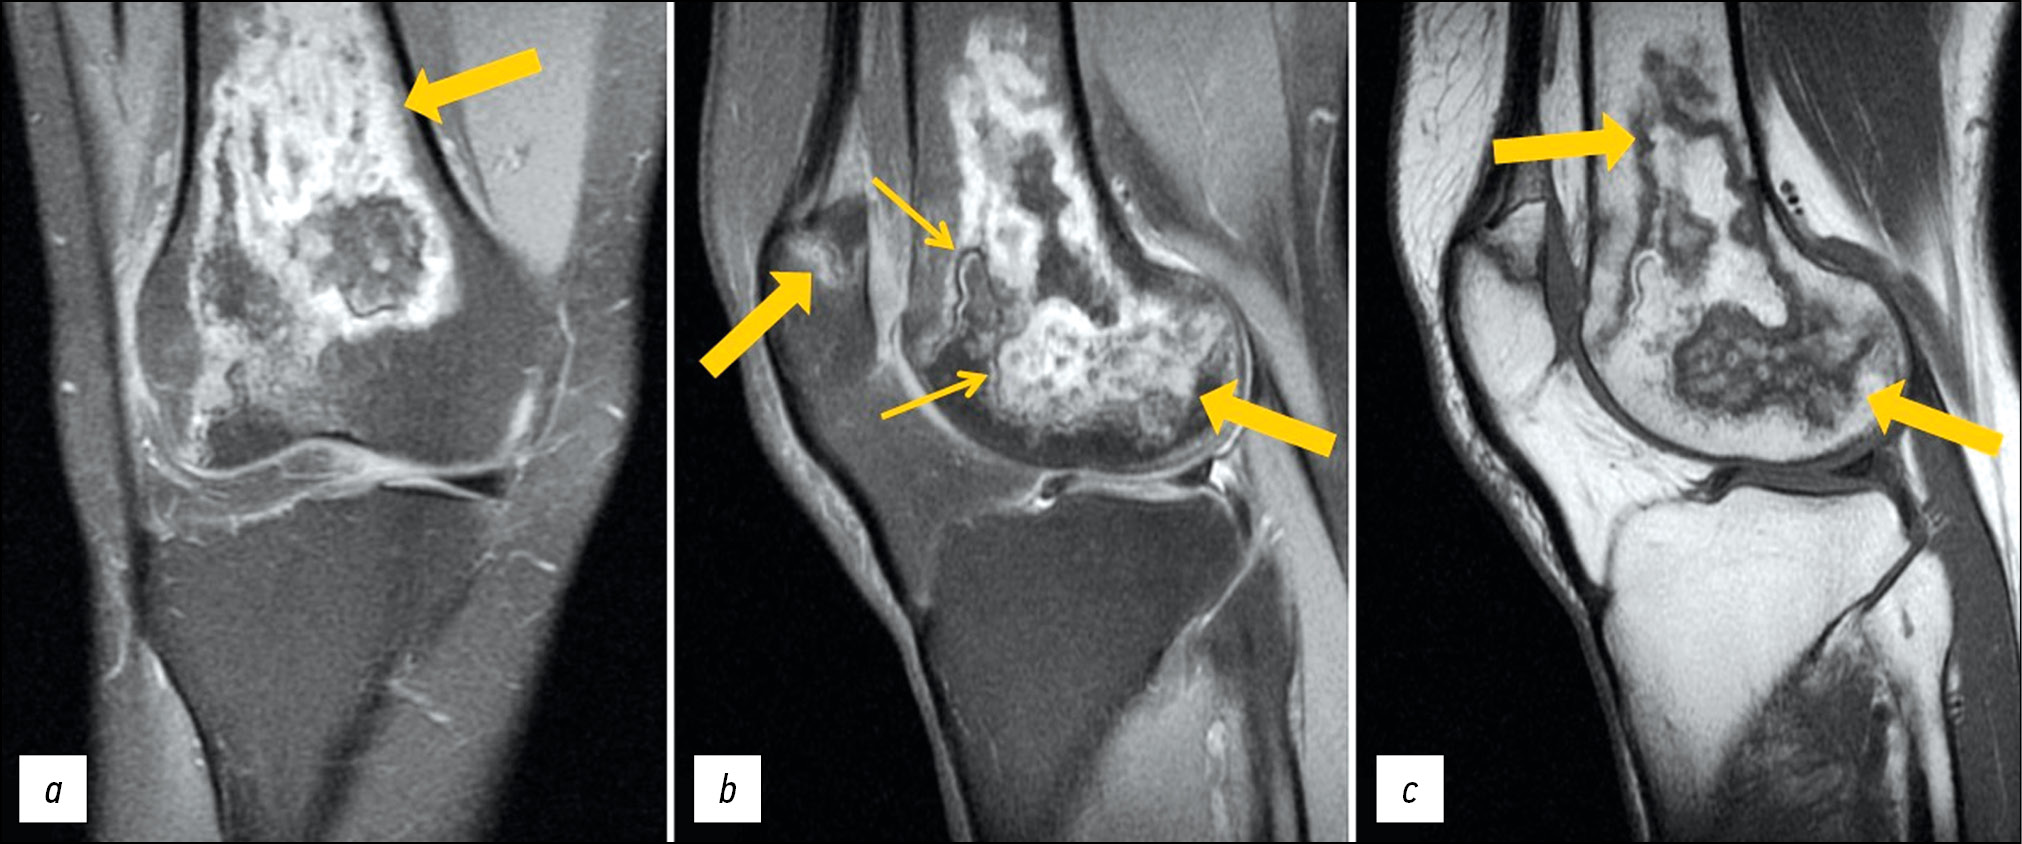

A follow-up MRI of both knee joints revealed positive changes: Previously identified lesions had become substantially less severe (Figs. 3 and 4).

Fig. 3. Follow-up MRI of the left knee joint: PDWI with fat suppression in the coronal (а) and sagittal (b) plane and T1WI in the sagittal plane (с). Thick arrows indicate areas of bone marrow edema in the form of a heterogeneous, irregularly shaped (“geographic”) MRI signal of femoral condyles and patella; the thin arrow indicates the “double line” sign in the form of internal hyperintense (granulation tissue) and external hypointense (osteosclerosis) lines on PDWI.